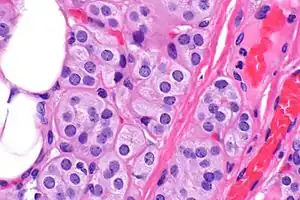

Microscopic image of a thyroid adenolipoma

Adenolipomas are diagnosed by surgical resection and examining the tumor with a microscope.[5] The presence of eccrine sweat glands are used to distinguish the tumor from a common lipoma. Size and the development of the capsule (tissue surrounding the tumor) can also aid in diagnosis. [6]